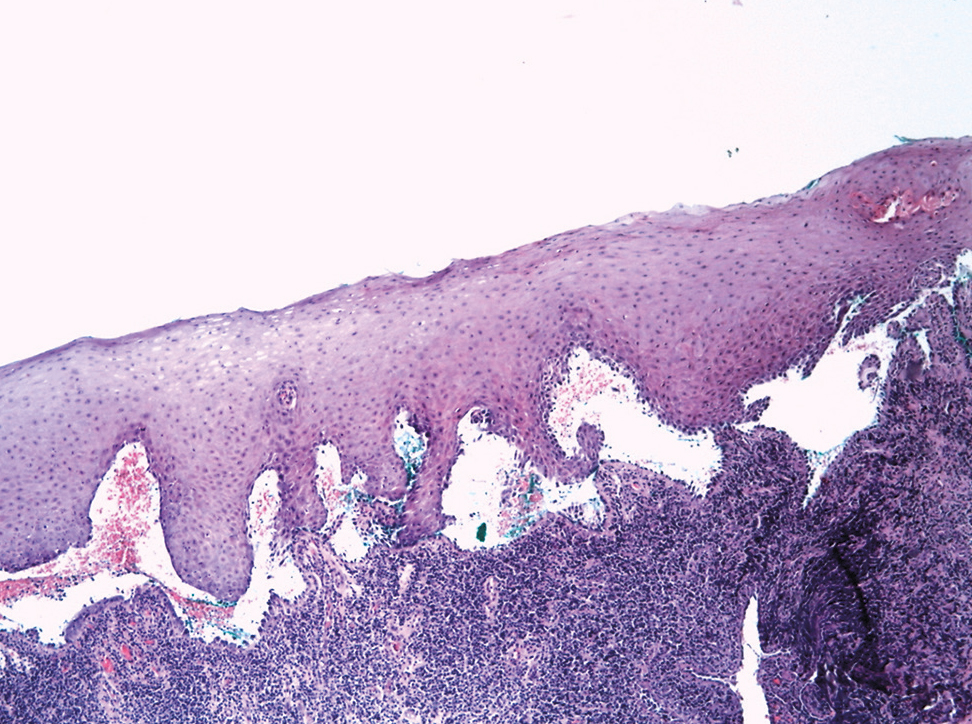

Патоморфологический метод используется для обнаружения акантолиза и локализации пузыря (рис. 4) [32]. На ранних стадиях пузырчатки при гистологическом исследовании биоптатов в очагах поражения могут определяться спонгиоз с экзоцитозом эозинофильных и нейтрофильных (у ряда больных) лейкоцитов в эпидермис и образование внутриэпидермальных микроабсцессов (рис. 5) [33, 34]. Таким образом, для окончательной постановки диагноза при характерной клинической картине, но в отсутствие убедительных гистологических данных следует применять метод прямой РИФ, демонстрирующий фиксацию IgG в различных слоях кожи (рис. 6) [32, 35].

Рис. 4. Гистологическая картина вульгарной пузырчатки: акантолиз на уровне шиповатого слоя, приведший к образованию внутриэпидермального пузыря.